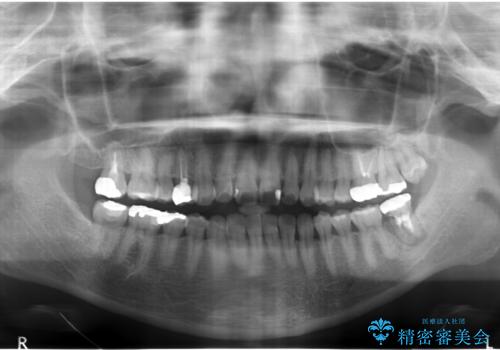

歯が割れた 親知らずの移植 30代女性

- 昔何回か根管治療した奥歯が膿んでいていて痛みがあることを主訴に来院された患者様です。

精査したところ、左下の奥歯にはひびが入っていて、保存不可能な状態でした。

義歯・インプラント・親知らずの移植の選択肢を提案したところ、移植をご希望されました。

割れている奥歯を抜去後左上の機能していない親知らずを移植し、生着したのち根管治療・補綴を行いました。